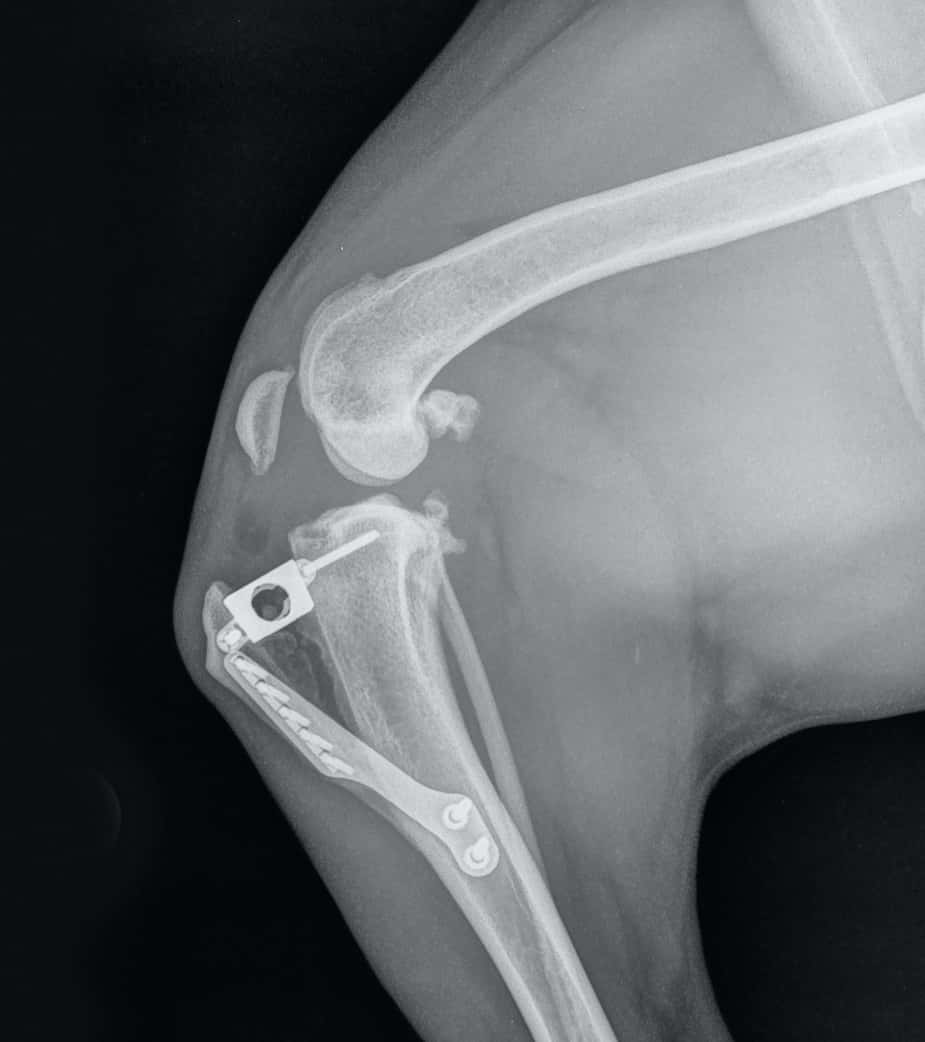

From dogkneeinjury.com

Roxie Xray Second Surgery Dog Knee Surgery and Ligament Injuries Arthroscopic Knee Surgery For Dogs veterinary arthroscopic surgery is gaining popularity, as clients increasingly are seeking minimally. the stifle (knee) joint is most commonly operated on, but the elbows, shoulders and intertarsal joints may also. In veterinary medicine, the use of arthroscopy has caught momentum over the last one to two decades and can be thought of as the “gold standard” when it. Arthroscopic Knee Surgery For Dogs.

From www.shutterstock.com

Xray Knee Dog After Tibial Tuberosity ภาพสต็อก 1810836481 Shutterstock Arthroscopic Knee Surgery For Dogs arthroscopic surgery offers several advantages over traditional open knee surgery, including smaller incisions, reduced pain, decreased risk of. uses of arthroscopy in dogs. arthroscopic surgery is the most reliable surgical procedure for treating knee, shoulder, and elbow injuries in dogs. veterinary arthroscopic surgery is gaining popularity, as clients increasingly are seeking minimally. the stifle (knee). Arthroscopic Knee Surgery For Dogs.